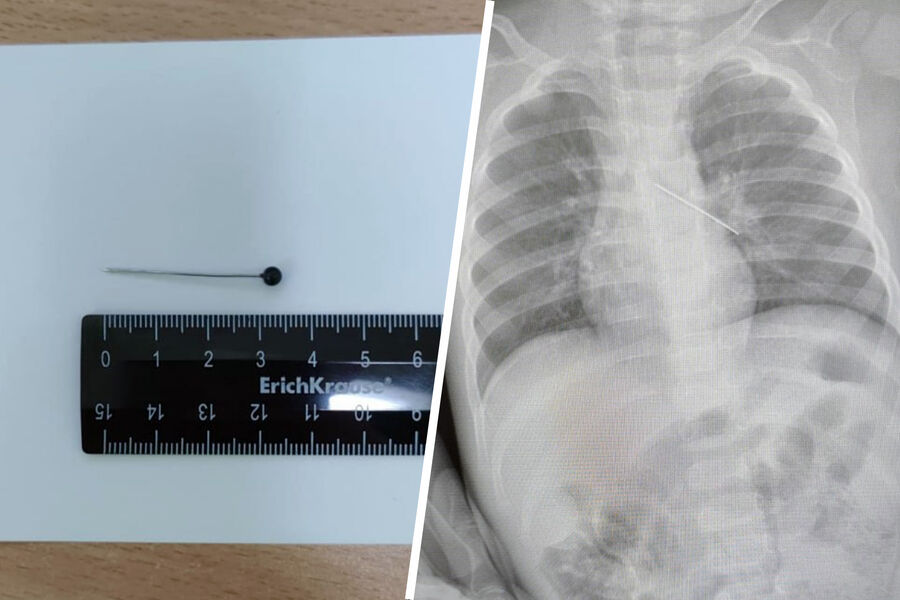

Врачи Центра охраны материнства и детства спасли 17-месячного ребенка, который из любопытства проглотил булавку. Об этом сообщила президент медицинского учреждения Лариса Белоцерковцева в Telegram-канале.

По словам медика, мать мальчика вовремя заметила беду и привезла ребенка в медицинское учреждение. Обследование показало, что инородный предмет зафиксировался в бронхах.

«Если бы бригада наших высокопрофессиональных специалистов не смогла удалить инородный предмет с помощью бронхоскопа, ребенка пришлось бы передавать торакальным хирургам для проведения большой операции», — пояснила Белоцерковцева.